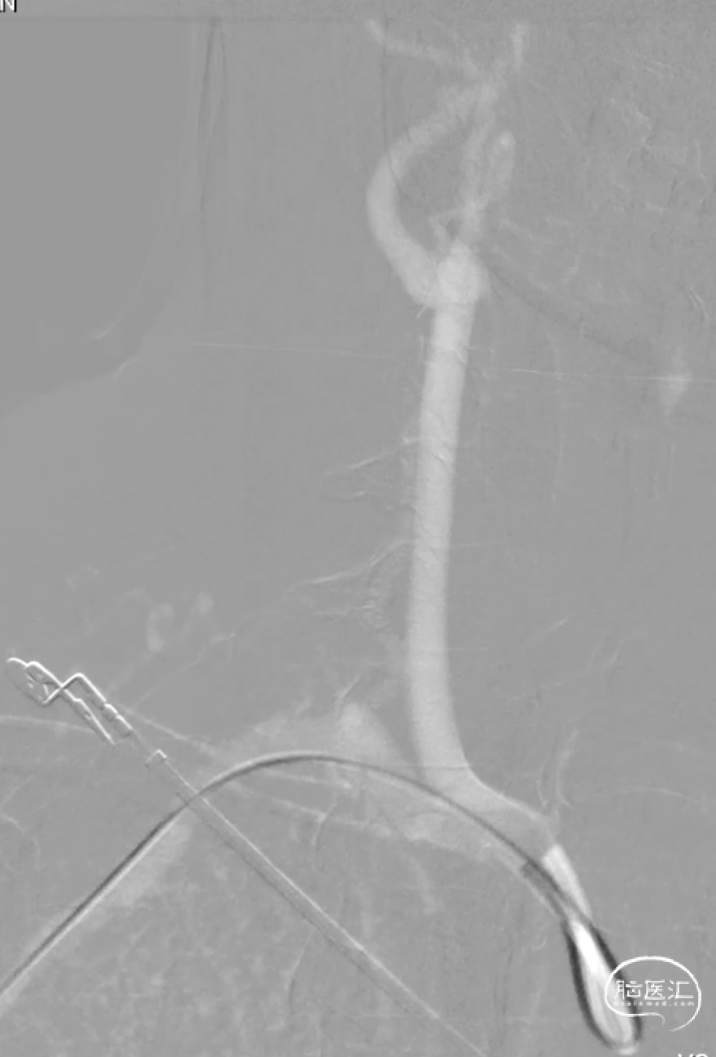

这是一根通桥银蛇DA远端通路导引导管,在Sim II和导丝到位后,通桥银蛇DA远端通路导引导管能够非常容易地顺着架设的道路直接放到位,然后进行后续使用Pipeline血流导向密网支架来治疗复发动脉瘤的操作。我们可以看到在Pipeline的到位以及释放的过程中,通桥银蛇DA远端通路导引导管都非常稳定,能够获得比较满意的结果。

释放PED过程中,通桥银蛇DA远端通路导引导管头端非常稳定。

这是一根115cm 通桥银蛇®颅内支持导管,通过R-DAS技术非常容易地放置到海绵窦段,手术过程中实际到达了海绵窦段后膝的位置,在这样的情况下释放血流导向装置就非常容易。

如下图病例所示,我们首先用R-DAS技术通过Sim II导管进行降主动脉成形,超选左侧颈总动脉,导丝到位,然后将银蛇DA远端通路导引导管放置到位,其到位后,后面的操作就至关重要,此时使用内部交换技术,将0.035"导丝保留在体内,将造影导管撤出。此时里边仍然有根0.035"导丝,然后再置入一根0.018"的加硬导丝,放置到位。0.018"导丝头端到达银蛇DA远端通路导引导管的头端,这个时候再撤出0.035"导丝,在整个过程中,银蛇DA远端通路导引导管内部一直有一根导丝在支撑,就可以完全避免导管打折。